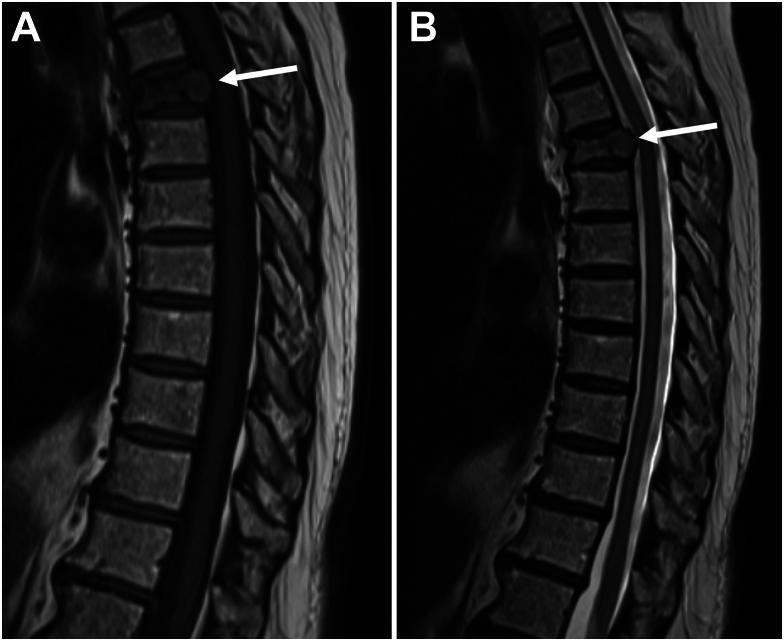

Vertebral hemangiomas (VHs) are common, benign angiomatous lesions of the spine with an incidence rate of 10% to 12% in the population. VHs have a characteristic appearance on imaging; however, a subset demonstrate atypical features that resemble more sinister pathologic processes, such as malignant neoplasms or metastatic disease. We report a case of an atypical VH that was initially thought to be a metastasis in a 75-year-old patient with a newly diagnosed pulmonary nodule. Our goal is to highlight the key findings of VHs on various imaging modalities that can potentially help minimize unnecessary investigations or interventions.

椎体血管瘤(VHs)是脊柱常见的良性血管瘤病变,在人群中的发病率为10%至12%。VHs在影像学上有特征性表现;然而,一部分显示出非典型特征,类似于更凶险的病理过程,如恶性肿瘤或转移性疾病。我们报告一例非典型VH病例,该病例最初被认为是一名75岁新诊断为肺结节患者的转移瘤。我们的目的是强调VHs在各种影像学检查中的关键表现,这可能有助于尽量减少不必要的检查或干预。